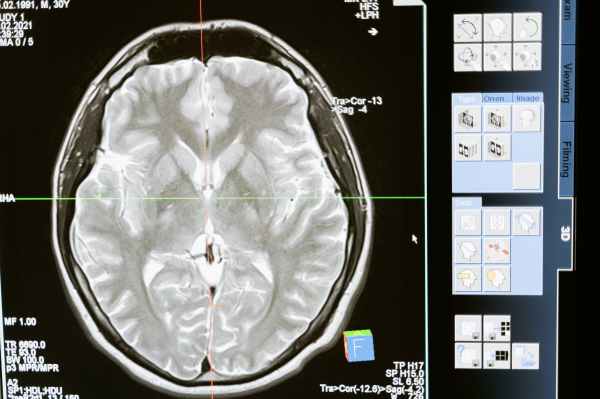

Our brain is shaped in three primary ways: temperament (inborn basic personality traits), genetics, and experience. Experiences of trauma, especially chronic childhood trauma, impacts how the brain develops and responds to threat in a number of ways. Our brain’s primary job is survival, and a brain that’s been through trauma is hypersensitive to threat. When... Continue Reading →